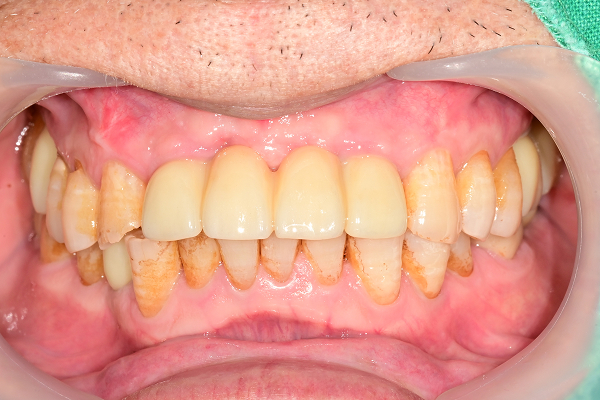

교합거상 케이스

- 마모·손상으로 낮아진 물림 높이를 정밀 분석 후 단계적으로 회복

- 턱관절·저작근 균형을 고려하여 기능과 심미를 동시에 개선